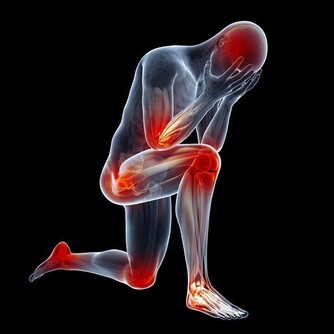

這時,病菌乘虛而入襲擊機體,容易引發各種呼吸系統疾病,導致感冒、氣管炎、關節炎等疾病。